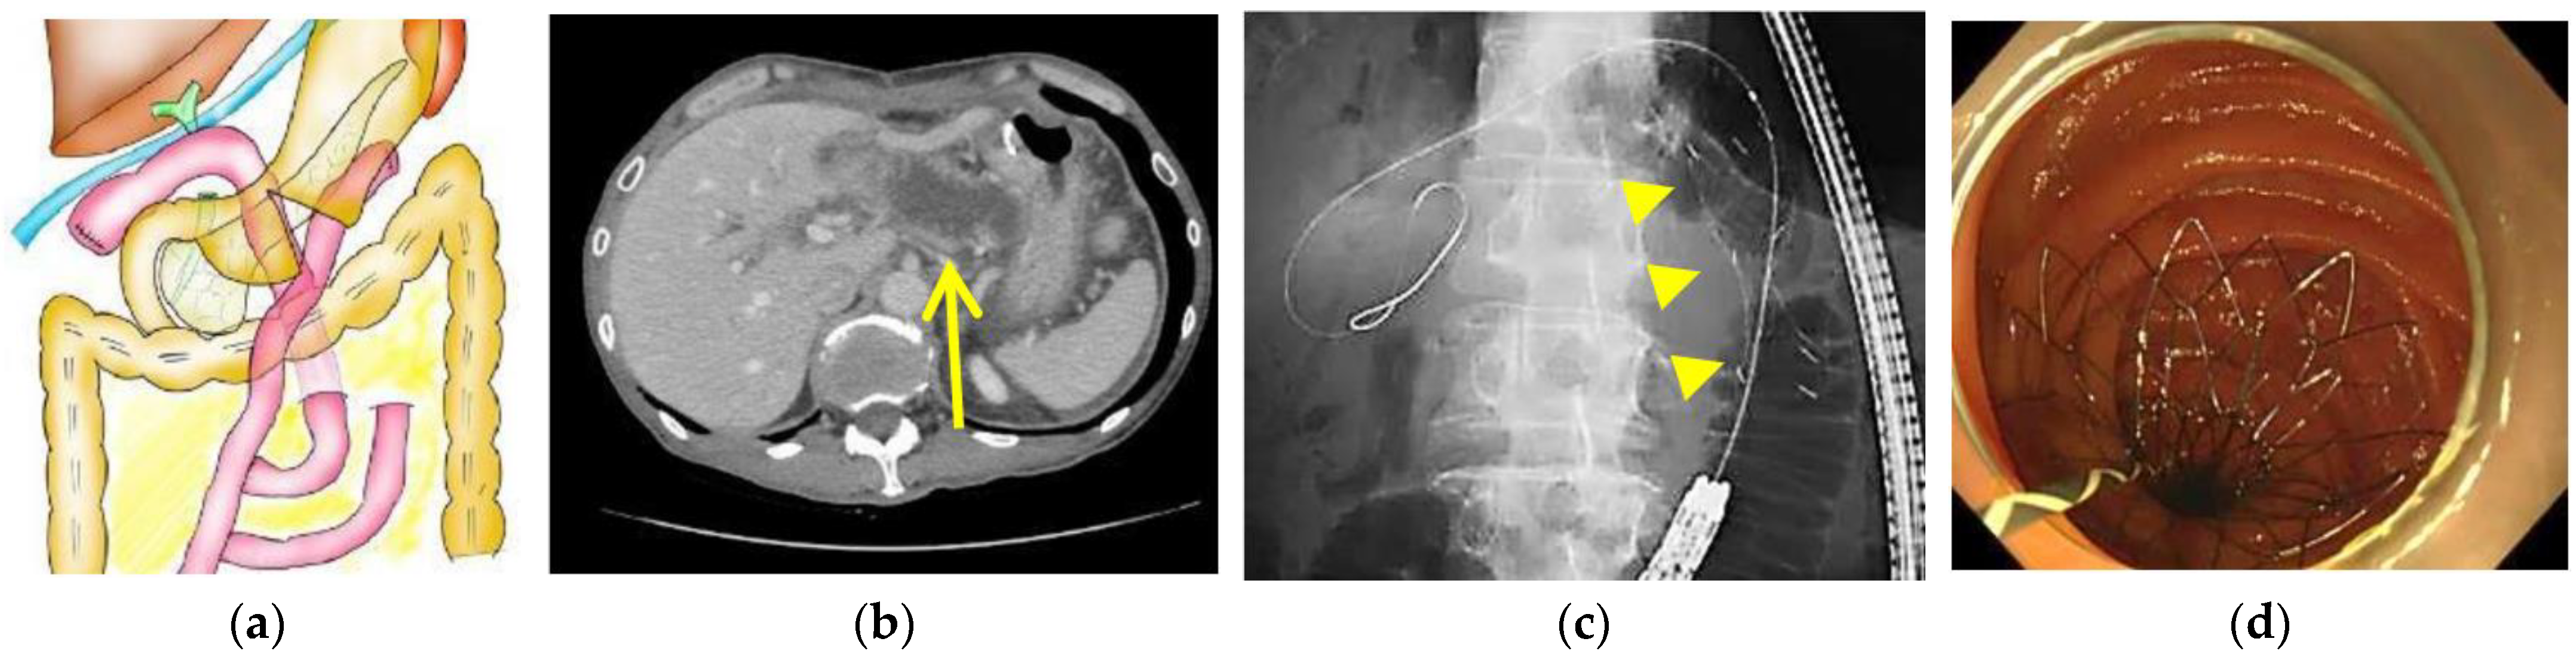

2.3. Endoscopic Procedure